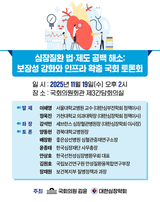

‘심장질환 법·제도 공백 해소: 보장성 강화와 인프라 확충’ 토론회 (11/19)

- 2025-11-12 08:43

- 노영희 기자